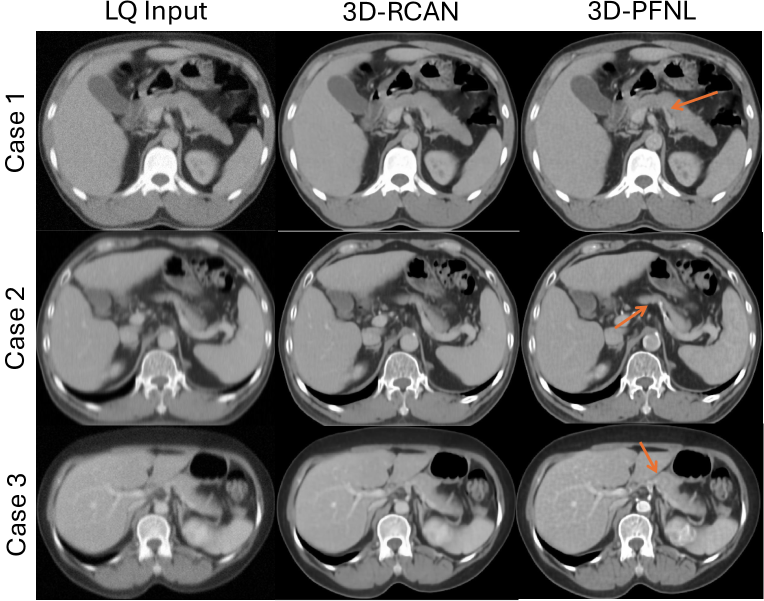

Refer to caption

Figure 2: Qualitative examples of low-quality (LQ) portal venous (PV) CT, 3D-RCAN restored PV CT and 3D-PFNL restored PV CT, respectively. Orange arrows indicate the sharper and clearer edges of the pancreas by the proposed 3D-PFNL quality enhancement approach.

As shown in Table I, both 3D-PFNL and 3D-RCAN models enhanced the quality of the LQ PV CT. There was very little difference (<<< 1%) between the 3D-PFNL and 3D-RCAN models. As seen in Fig. 2, the proposed 3D-PFNL method recovered sharper edges of the pancreas, whereas the 3D-RCAN model over-smoothed the edges of the pancreas. Of note, the edge reconstruction loss used in the 3D-PFNL model shifted the focus from perceptual quality to structural enhancement. This is in contrast to existing restoration models [25, 17, 18] that are optimized by the L1subscript𝐿1L_{1}italic_L start_POSTSUBSCRIPT 1 end_POSTSUBSCRIPT reconstruction loss alone. However, an increase in quality does not necessarily mean that it can facilitate downstream tasks, such as segmentation.

However, there was no significant difference in the performance between the two models. This can be attributed to the small number of patients (n = 16) in the test data subset, and it is the major limitation of our work. Another limitation is the introduction of artifacts on the portal venous phase CT. 3D-PFNL attempted to fuse information from the three phases to reconstruct a high-quality PV phase. As shown in case 3 of Fig. 2 and Fig. 4, the contrast of the aorta was enhanced in the portal venous phase, but it is not a feature of this phase. Furthermore, low-quality PV CT was simulated through intensity-based degradations, and the proposed model was trained and evaluated on the same VinDr dataset. The generalizability of the model to external datasets (e.g., low-dose CT) is currently undetermined. In the future, validation of the approach on a larger sample size and with additional organs and structures is necessary.